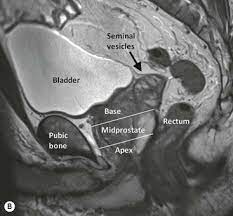

21+ Sagittal Prostate Mri Anatomy. From right to left iliac fossa including internal obturator muscle. Parallel to the base of urinary bladder).

Strictly sagittal to the body axis. Prostate mri has become an increasingly frequent examination faced in daily radiological practice and is usually acquired as either multiparametric or biparametric mri of the prostate. The coronal view is from the top, showing the left and right sides of the gland.

Anatomical changes during physiological voiding in men. The probe is angled from one side. The important role of magnetic resonance imaging (mri) in the anatomic evaluation, detection, and staging of prostate cancer is well established. Axial t1wi of pelvis 2.